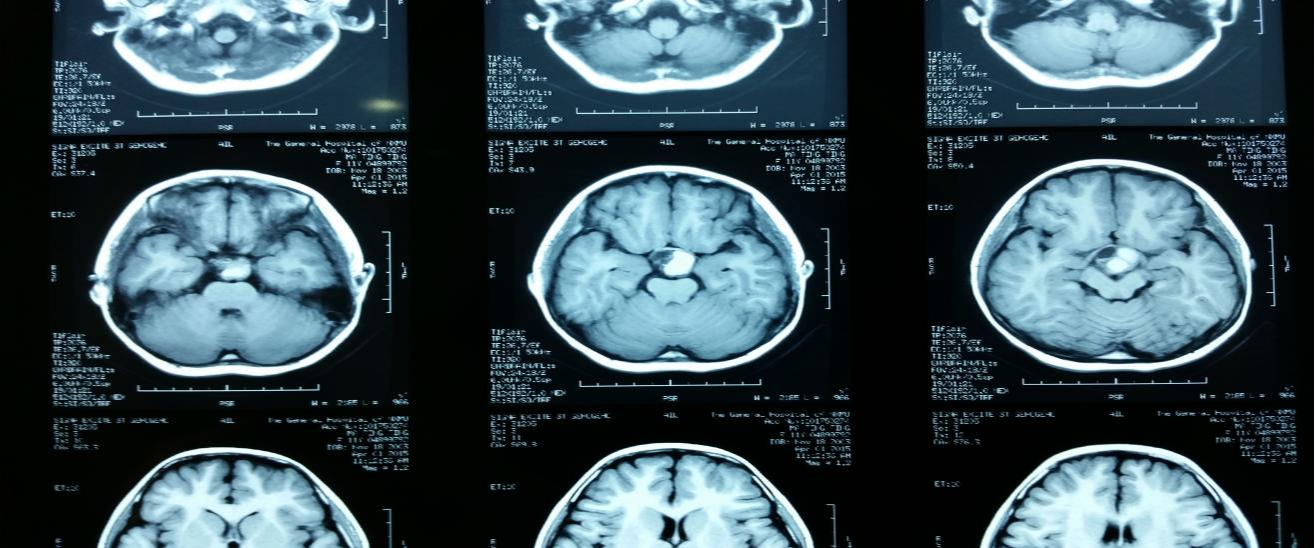

今天來了一個小姑娘,看起來8、9歲這樣,結(jié)果一看就診信息這個孩子已經(jīng)11歲了,患者的家屬和我們敘述了小姑娘發(fā)生的變化,首先是覺得孩子好像停止了生長一樣,個子矮小,然后發(fā)現(xiàn)孩子的反應力變得遲鈍,最近又發(fā)現(xiàn)孩子的視力變差,所以想來醫(yī)院查明孩子發(fā)生了什么。根據(jù)家屬的敘述,我們選擇先檢查頭顱CT,查看是否是顱內(nèi)病變導致的。結(jié)果CT顯示:鞍區(qū)占位,部分向鞍上發(fā)展,部分向鞍后上斜坡延伸。密度混雜。囊性,周邊鈣化,狀似“蛋殼”,“蛋殼”內(nèi)有小塊狀高密度鈣化灶。強化不明顯,初步懷疑為顱咽管瘤的可能。

該患者入院后,術(shù)前頭顱MRI進一步檢查,影像顯示病灶明顯不均勻強化,邊界清楚。做好術(shù)前準備后,根據(jù)患者占位的部位,選擇經(jīng)額顳、視交叉后間隙入路切除腫瘤。術(shù)中觀察瘤體呈現(xiàn)出紅褐色,部分黃褐色囊液,吸出囊液。并分塊切除囊壁和鈣化成分。最終確診為顱咽管瘤(囊實性)?;颊咴谑中g(shù)后1小時清醒,情況良好,所以回到病房繼續(xù)觀察身體情況,是否出現(xiàn)后遺癥等。

顱咽管瘤切除術(shù)治療以切除腫瘤,保護視神經(jīng)和其他神經(jīng)為準則。術(shù)后小患者情況良好,回到病房觀察與腫瘤切除前對比,視力沒出現(xiàn)減退,眼運動正常,沒有電解質(zhì)紊亂、意識障礙等后遺癥。在手術(shù)后3日內(nèi)發(fā)現(xiàn)尿量偏多,但沒有對日常生活造成影響。手術(shù)后6天復查影像CT顯示:瘤體消失,少許鈣化斑遺留。雖然手術(shù)盡量全切為好,但是如果如實難切,遺留少部分鈣化斑也是可以的?;颊咝g(shù)后情況良好,未出現(xiàn)后遺癥,遂在住院7天后出院。